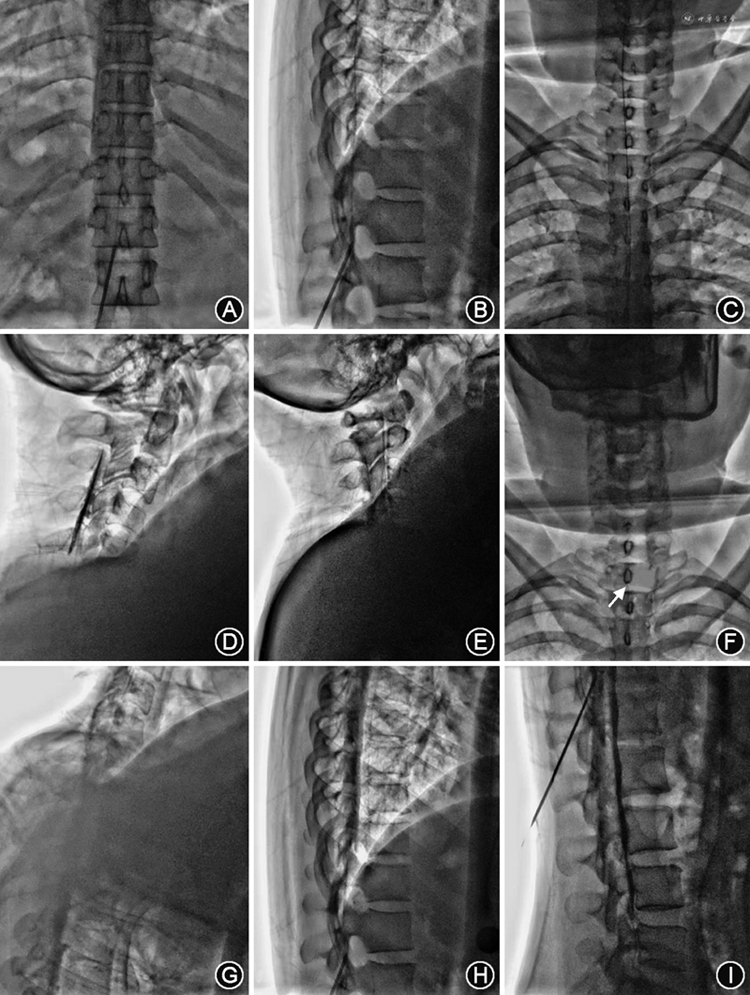

穿刺点一般选择最低漏点尾侧1~2个间隙处或直接选择腰段。采用旁正中斜向上穿刺入路,此入路更安全,也更有利于置管。穿刺针到达硬膜外腔后,经穿刺针置入导管,数字减影血管造影(DSA)机/C臂下验证导管位置,直至导管尖端位于最头侧漏点附近,再次造影确认导管尖端位于硬膜外腔。缓慢推注封堵液(自体血与造影剂比例为4∶1),直至DSA机/C臂下可见头侧漏点完全覆盖,回退导管至封堵液未覆盖的位置,重复前一步骤注入封堵液,直至封堵液完全覆盖漏点区域(图3)。注射过程中应反复询问患者有无头痛、头胀及恶心等不适。注射结束后,拔除穿刺针及导管,无菌敷料覆盖。置管时操作要轻柔,如遇阻力切勿暴力通过,以避免撕裂硬膜造成新的漏口。